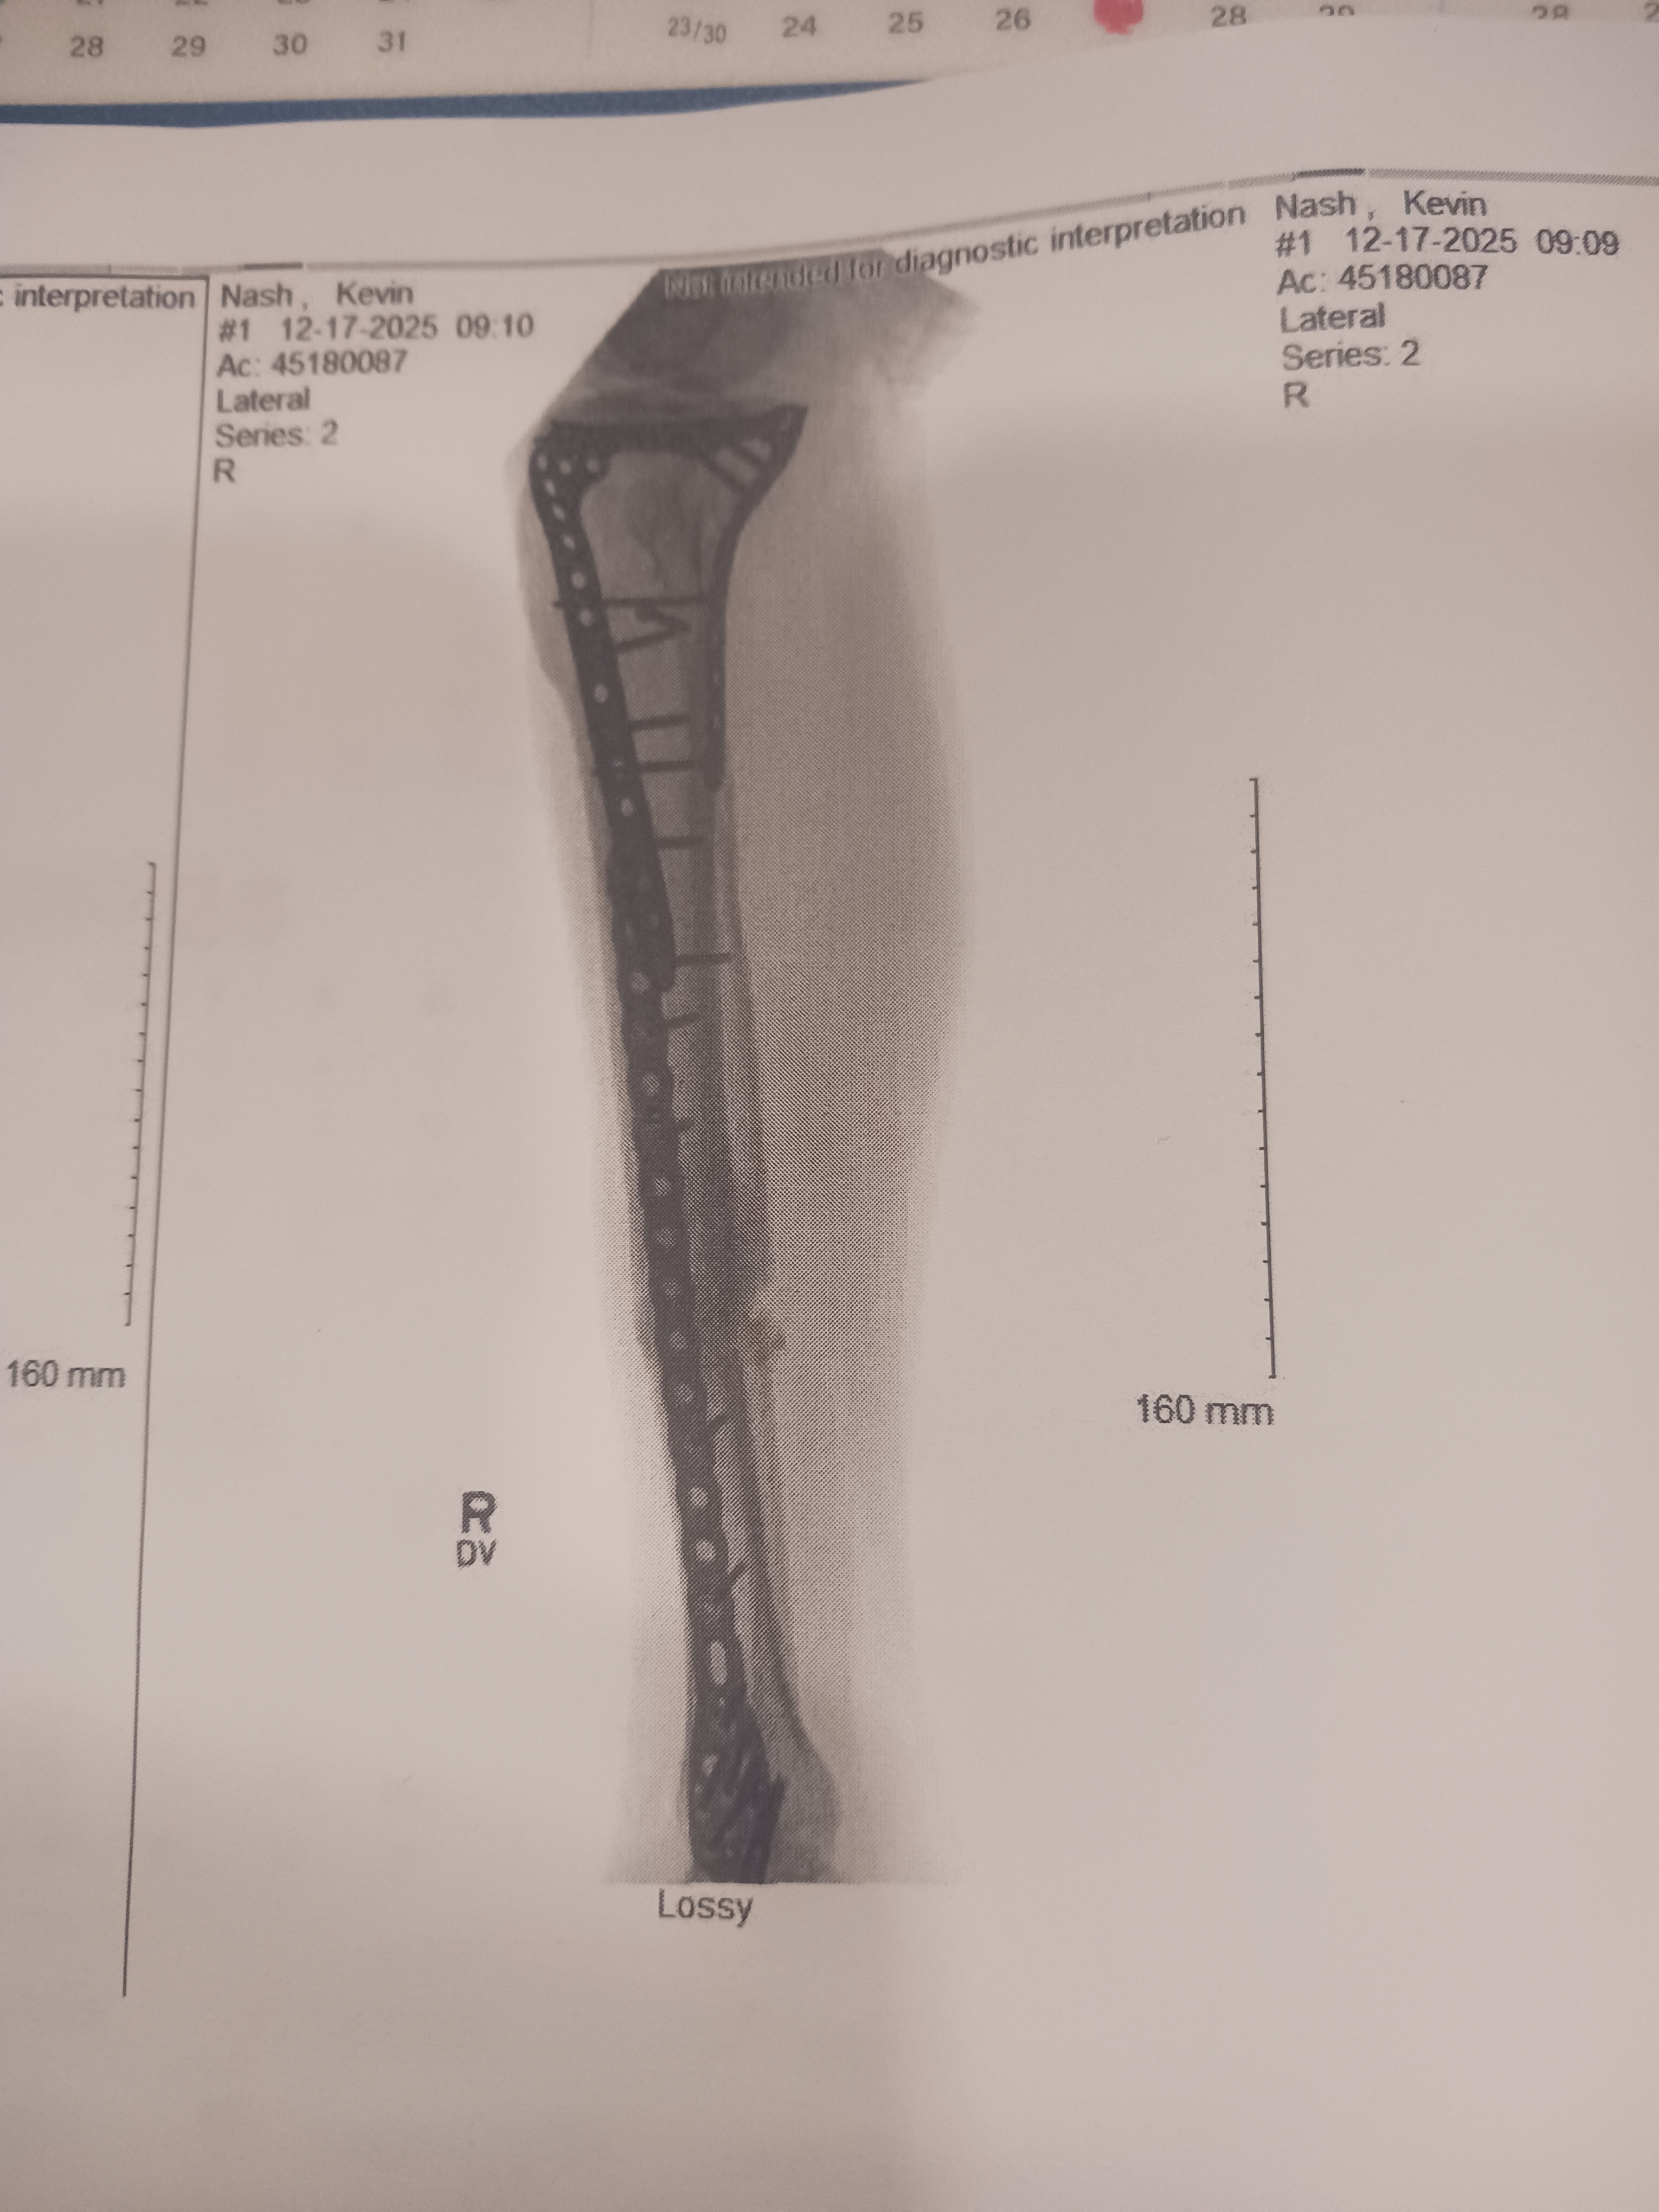

Hello, as most of you already know, on July 1st this last year, I had a bicycle accident that resulted in me breaking my leg. It was a Tib/Fib compound fracture. I was hospitalized until July 3rd, during which time I had surgery. Plates and screws were implanted to fix my leg. I have not been allowed to return to work yet, although it's looking like I got a letter today(12-26-2025) that I can go back to work! Thankfully! I just need to get over this last bump and I'll be alright!